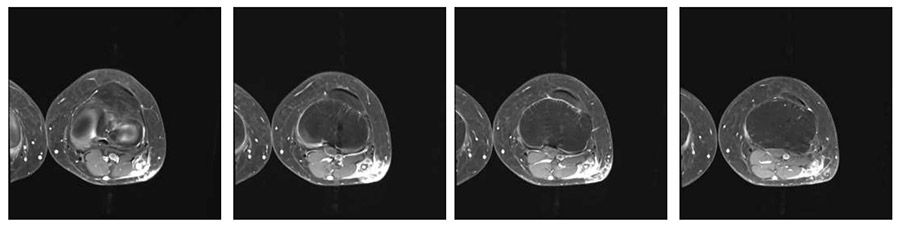

Ameliyat Öncesi: İlk ameliyat sonrası kontrol MR’da kalıntı tümör dokusu ve çevreleyen ödem görülmekte